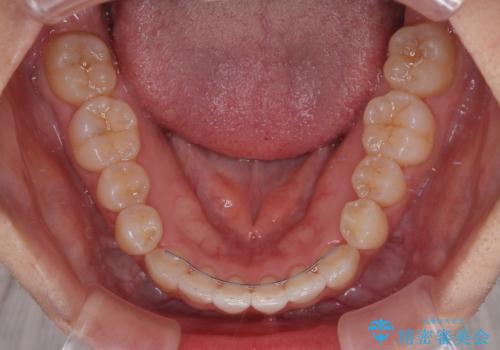

- 上下前歯のデコボコを気にして来院された患者様です。

インビザラインによる上下歯列の拡大と、IPR(歯と歯の間を削る)にるスペースの獲得により、前歯のデコボコを改善することとしました。

下顎前歯は後戻りを起こしやすいため、舌側を細いワイヤーで固定し、マウスピース型リテーナーで保定を行うこととしました。